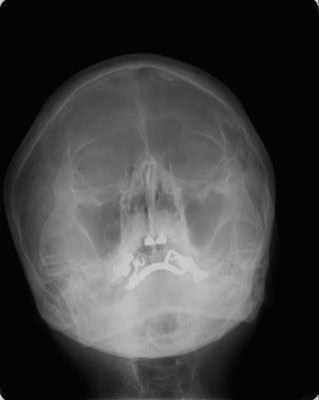

1.上顎洞穿刺

鼻の中から、頬の上顎洞に太めの針をさし、食塩水などで上顎洞の中を洗浄します。洗浄後にステロイド剤や、抗生剤を上顎洞の中に注入します。

3回ほど行うと綺麗になります。前に開けた孔を用いて穿刺針を通し、洗浄することができるので、2回目以降は少し楽になります。

2.上顎洞以外の洗浄

上の方法で洗えない篩骨洞や前頭洞にはプレッツ法という洗浄の方法もあります。